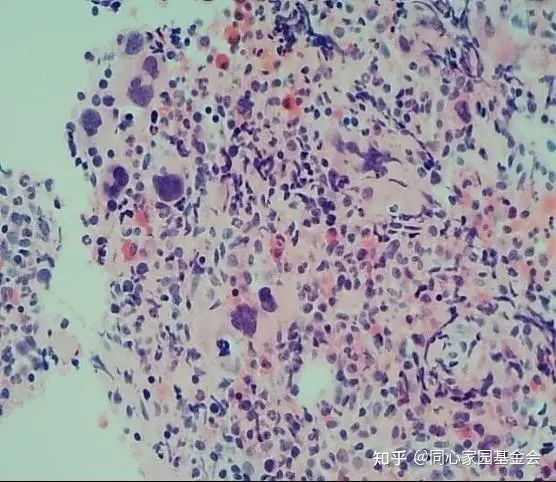

骨髓活检报告如图3-4:镜下描述:骨髓有核细胞增生过度(造血面积占约95%);粒/红比例增高;粒系增生,以较成熟阶段细胞为主,偏幼稚细胞散在少见;红系以中晚幼红细胞为主;巨核细胞散在易见,易见核深染、畸形、分叶少巨核细胞,部分呈“气球样”;淋巴细胞散在可见;浆细胞偶见;骨髓间质可见网状纤维增生。免疫组化:CD34幼稚细胞偶见(+);CD68幼稚细胞偶见(+);CD61巨核细胞(+)。符合原发性骨髓纤维化——纤维化前期(Pre-PMF),请结合临床及其它相关检查等。

图3 骨髓活检H-E染色10倍

注:1、原幼细胞比例小于5%;2、MF-1级;3、未见明显的胞体大、分叶多的巨核细胞,未见“鹿角状”巨核细胞;4、巨核细胞簇状、散在多见,易见核深染、畸形、分叶少巨核细胞。JAK2基因V617F突变定量检测(Q-PCR)结果:阳性。